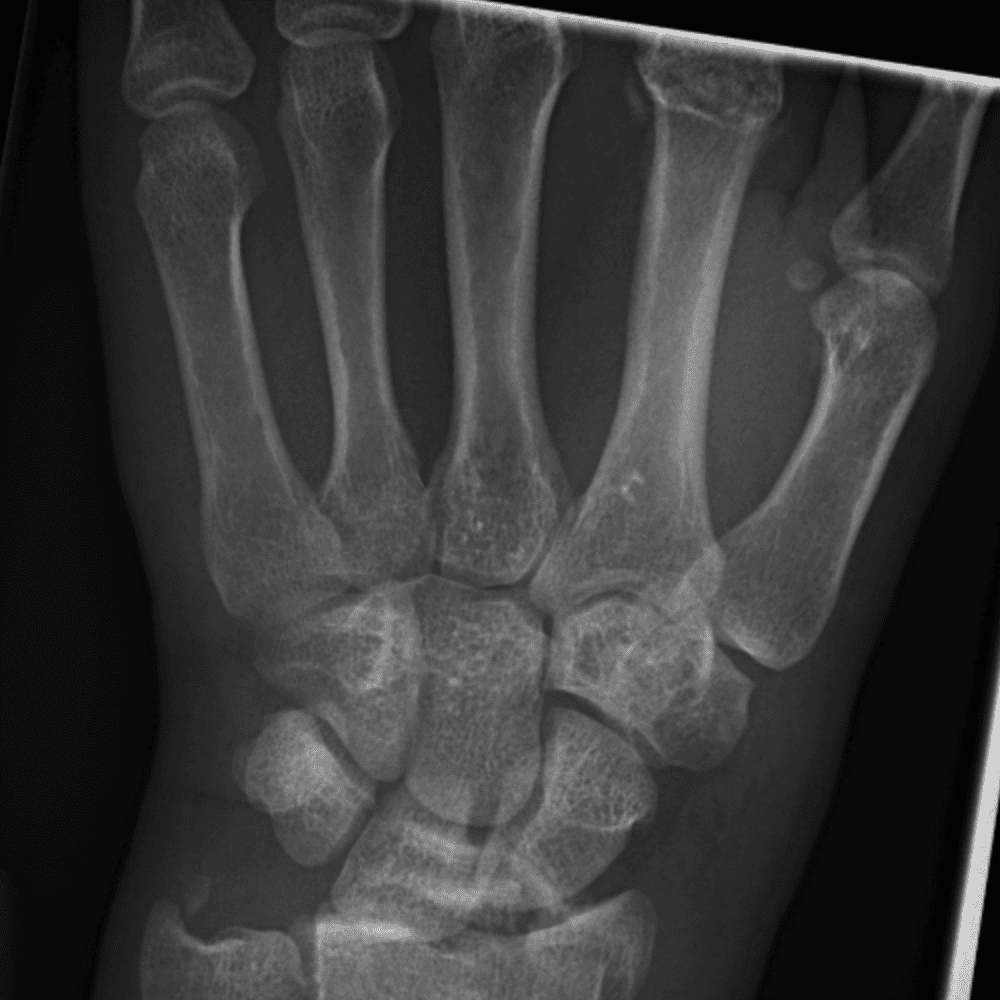

Simuliert den Dienst durch subtile oder schwierige Fälle und einige Normalbefunde.

30 Fälle